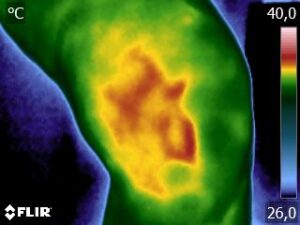

Como no caso da sequência de termogramas abaixo de uma paciente do sexo feminino, 42 anos, sem comorbidade e que apresentou dor em joelhos após treino de musculação. Foi realizado uma Análise Termofuncional e detectado alterações térmicas condizentes com o relato de dor.

Estas informações foram a oportunidade para convencer a paciente a realizar uma ressonância magnética para determinar o grau de comprometimento tecidual. Pois sem isso, após a melhora da dor, a liberação de carga e até a carga terapêutica ficariam limitadas.

Já com este conhecimento foi possível determinar um tratamento que abarcasse as áreas de dor e as áreas de comprometimento tecidual que apresentam inflamação, até a paciente retornar com o resultado da ressonância.

Isso adianta e muito a reabilitação, pois oferece informação que a olho nu não seria possível.